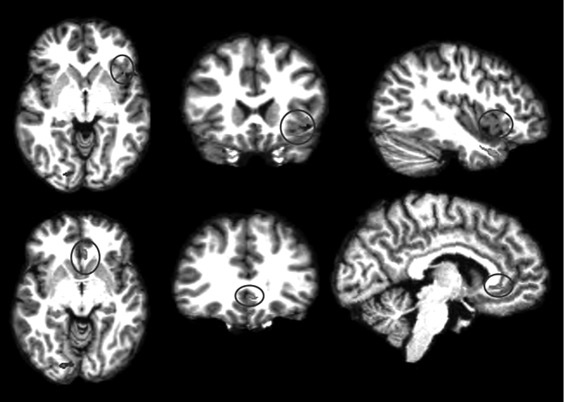

Анализируя далее научную литературу, мы пришли к выводу, что процесс поведенческого подражания с участием верхних отделов височной коры и эмоциональный (физиологический) резонанс, требующий участия островка, тоже имеют отношение к системе зеркальных нейронов. При подражании верхние отделы височной коры кодируют сложные процессы сенсорных следствий двигательных актов; при эмоциональном резонансе островок осуществляет физиологический и аффективный сдвиг, имитирующий его у другого человека. Исходя из параллелизма этих функций реципрокного действия (имитационной, физиологической и аффективной), мы можем использовать термин «резонансный контур», подразумевая, что в нем могут участвовать зеркальные нейроны, но не все компоненты этого контура двигательные, поэтому формально мы не можем назвать такой контур зеркальным. В нашем обсуждении мы примем во внимание это отличие и будем называть резонансный контур именно так, или будем прибегать к выражению «области, связанные с системой зеркальных нейронов» (рис. П.1 и П.2).

П.1

П.2

Рис. П.1, П.2. Функциональная МРТ, выполненная во время выполнения медитации осознавания дыхания. На снимках видна активация верхней височной извилины (рис. П.1) и активация островка и вентрального отдела передней поясной извилины (рис. П.2). Верхняя височная кора, островок и области срединной префронтальной коры (показанные здесь) вместе с системой зеркальных нейронов, как предполагается в тексте, содержат элементы «резонансного контура», которые активируются в ходе внимательного осознавания (снимки напечатаны с разрешения Сары Лазар © 2005)